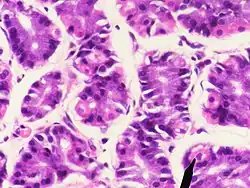

Human parietal cells (pink staining) – stomach.

Parietal cells are part of fundic gland polyps (here shown in high magnification).[9]